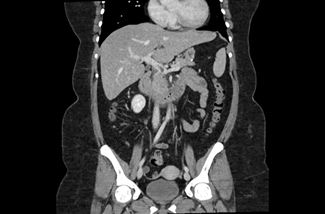

The initial physical examination showed a patient in discomfort but with normal vital signs. The abdominal palpation revealed epigastric tenderness without guarding or without other signs suggestive of acute abdomen. Surgical sites appeared to be well-healed, clean, and dry with no evidence of drainage or dehiscence. The laboratory analyses showed elevated inflammatory parameters (13,500 leukocytes and a C-reactive protein level of 123,20 mg/dL) and normal levels of amylase and lipase. A contrast-enhanced abdominopelvic computed tomography (CT) scan (Figures 1, 2, and 3) showed a dilatation in the mesenteric vessels, particularly the superior mesenteric vein, which had a luminal filling defect near its confluence with the splenic vein. The CT scan also revealed thickening of the adjacent adipose tissue, albeit without signs of intestinal ischemia. The patient was admitted to ward and started on LMWH 100 mg every 12 hours along with reinforced IV hydration. After three days in the hospital, she was discharge home asymptomatic. Anticoagulation therapy was continued with LMWH for one month before transitioning to a non-vitamin K antagonist oral anticoagulant (NOAC), specifically Apixaban 5 mg every 12 hours, and the use of estrogen for birth control was discontinued. At the three-month follow-up, the patient had lost 20 kg and was scheduled to repeat the CT scan and to discontinue anticoagulation therapy approximately six months after the thrombotic event.

Figure 1 CT showing a luminal filling defect in the superior mesenteric vein – coronal image.